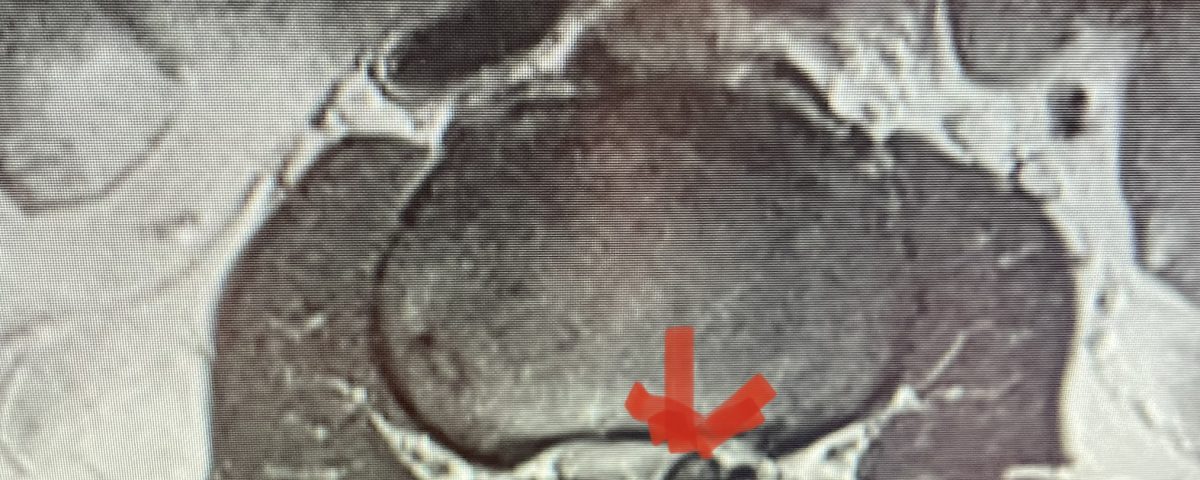

Lateral recess stenosis typically involves compression of the nerve root as it takes off from the thecal sac, prior to entering the nerve foramen or tunnel. In lateral recess stenosis there is narrowing of less than 5 mm between the facet superior articulating process and the posterior vertebral margin and is bounded laterally by the pedicle. The nerve root gets caught medial to the pedicle. The nerve is compressed commonly from thickened ligamentum, short pedicles, or in particular an enlarged superior facet process which compresses the nerve as it descends prior to going underneath the pedicle in a region that is designated as the subarticular recess. (Figs 1, 2, and 3) With lateral recess stenosis, for example, of the L4-5 subarticular recess, the descending L5 nerve root will be compressed by the corresponding L5 superior facet. With foraminal stenosis the actual nerve root is compressed beyond the medial pedicular zone which can be caused by a far lateral type disc facet hypertrophy, tumor, or subluxation.

Figure 1: Axial lumbar spine images demonstrating the descent of the nerve root below the subarticular recess as it rounds the pedicle and enters the neural foramen. On the left shows the normal anatomy and on the right showing the descending nerve root being compressed in the lateral recess by a hypertrophied superior process with medial protrusion.

Figure 2: Cartoon axial image of the lumbar spine showing (arrow) severe narrowing of the lateral recess with flattening of the nerve root compared to a normal nerve root on the opposite side.